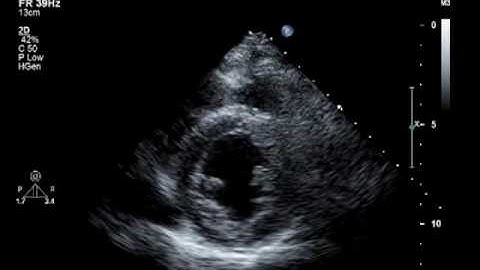

SAX View Interpretation – Wall Motion Patterns #WallMotion #GlobalHypokinesia #RWMA #LVFunction